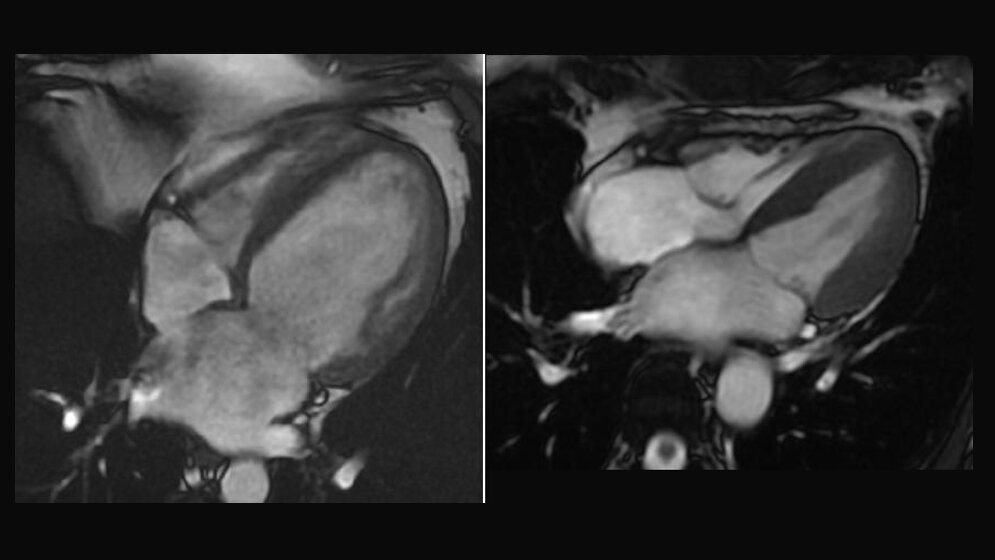

Im Zentrum stehen zwei Formen der Herzschwäche: die dilatative Kardiomyopathie (DCM) und die hypertrophe Kardiomyopathie (HCM). Bei beiden kann das Herz schlechter pumpen, die Gründe sind jedoch verschieden. Bei der DCM ist die linke Herzkammer ausgedehnt wie ein mit Wasser gefüllter Luftballon. Die HCM hingegen kennzeichnet, dass sich die Wände der Herzkammer verdicken. Die Forscher wissen, dass bei beiden Prozessen die Herzmuskelzellen verändert und dass auch Bindegewebszellen beteiligt sind.